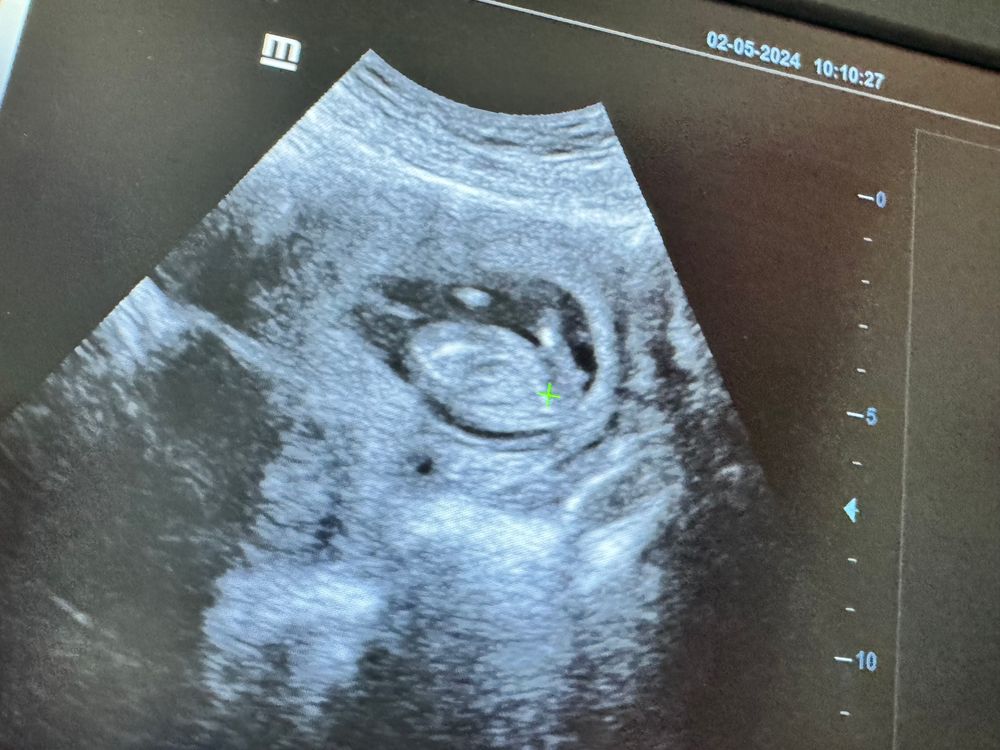

УЗИ в 13 недель

по этому фото непонятно, если честно 😅

Анна, напротив плюсика видите белое как точечка

Саяна , тут сложно сказать. Обычно я сразу вижу по бугорку, но это когда малыша полностью видно 😄

Ребеночек 😂 Так сложно очень определить , даже врачу узисту на таком сроке Недель в 15 смогут сказать

Елизавета , тут многие по бугорку отпределяли поэтому решила посмотреть а вдруг и мне смогут